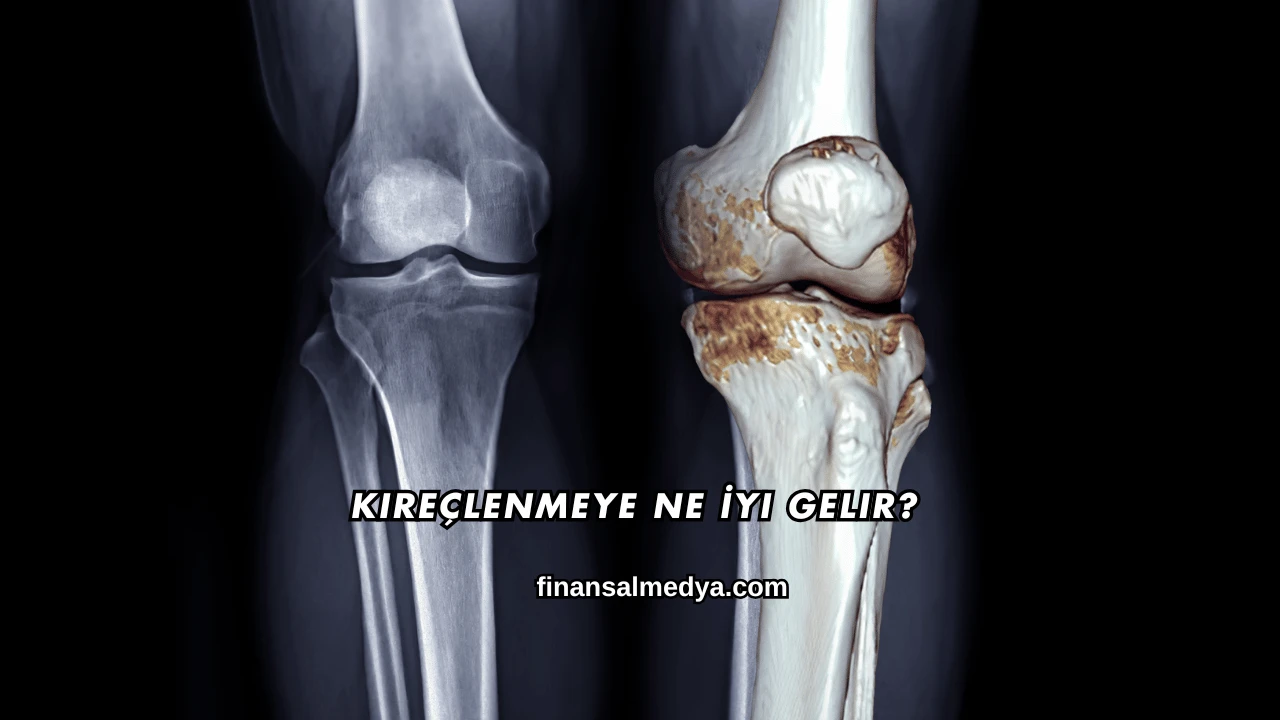

Kireçlenme, tıp dilinde osteoartrit olarak bilinen ve eklemlerde kıkırdak dokusunun aşınmasıyla ortaya çıkan bir rahatsızlıktır. Genellikle ileri yaşlarda görülen bu durum eklem ağrısı, tutukluk ve hareket kısıtlılığına yol açar. Kullanıcılar kireçlenmeye ne iyi gelir sorusuna yanıt ararken doğal yöntemler, ilaç tedavileri ve yaşam tarzı değişikliklerini merak etmektedir.

Kireçlenme, eklemlerde bulunan kıkırdak yapının zamanla yıpranması ve incelmesi sonucu ortaya çıkan bir eklem hastalığıdır. Bu durum en çok diz, kalça, el ve omurga eklemlerinde görülür. Eklemlerde ağrıya sebep olan bu hastalık günlük yaşamı zorlaştırır ve ilerleyen dönemlerde ciddi hareket kısıtlılıklarına yol açabilir.